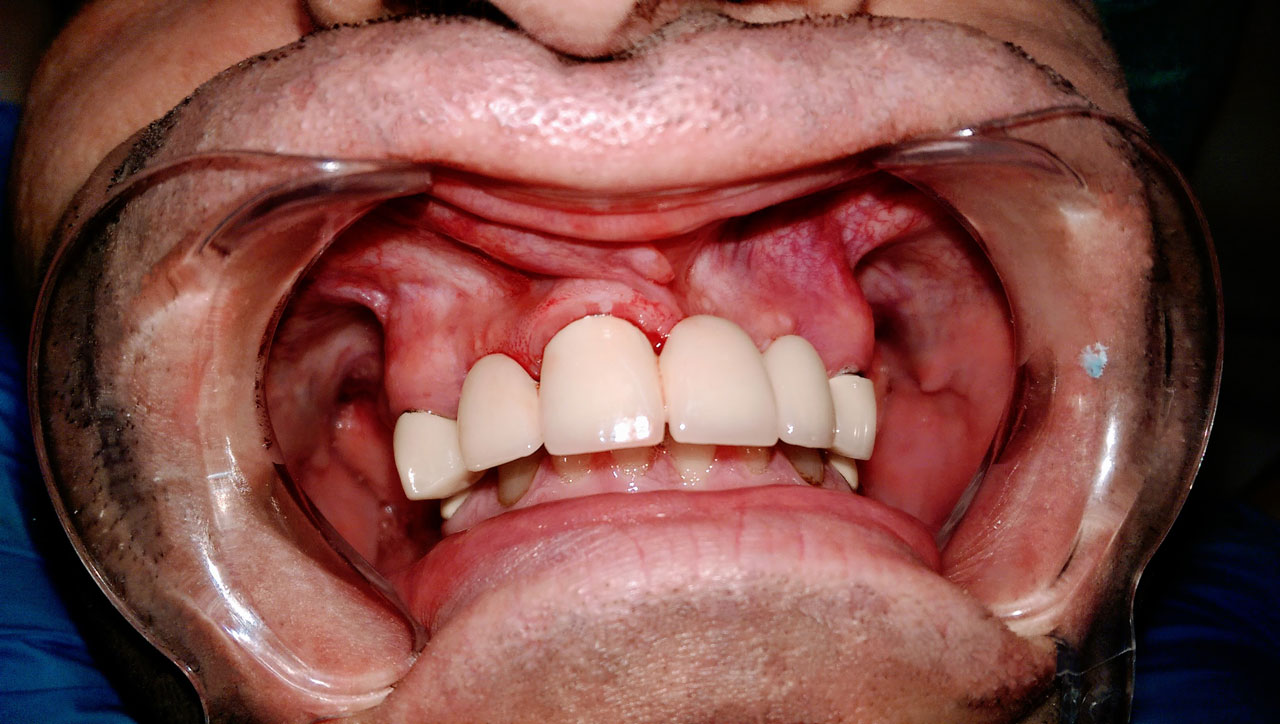

Teljes fogatlanság helyreállítása 2 nap alatt

Teljes fogatlanság helyreállítása 2 nap alatt azonnal terhelhető svájci IHDE implantátumokkal és PMMA műanyag hidakkal. Intraorális szkennerrel vettünk lenyomatot az implantáció után, és erre a digitális mintára készítette el a fogtechnika a hidak digitális tervezését, majd faragta ki műanyagból. Ezt a gyors munkát az azonnal terhelhető implantátumok és a digitális lenyomat, tervezés segítségével tudtuk megcsinálni mindössze 2 nap alatt. Dr. Kelemen Péter és a Symbion Fogtechnika munkája.